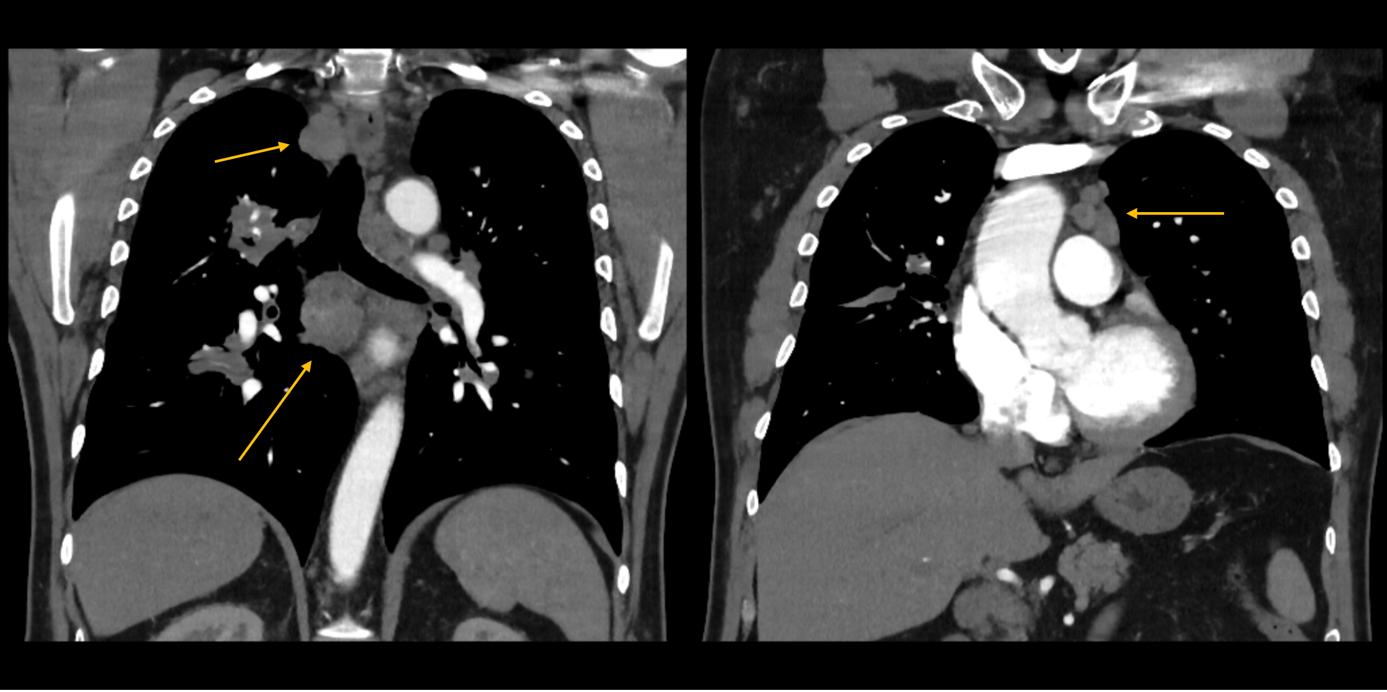

Aufgrund des pulmologischen Befundes wurde eine Computertomographie veranlasst. Im Weichteilfenster zeigten sich massiv vergrößerte mediastinale und bihiläre Lymphknoten (gelbe Pfeile). Im Lungenfenster zeigten sich multiple, zum Teil scharf abgrenzbare, Rundherde, zum Teil grobfleckige Infiltrate (blaue Pfeile).